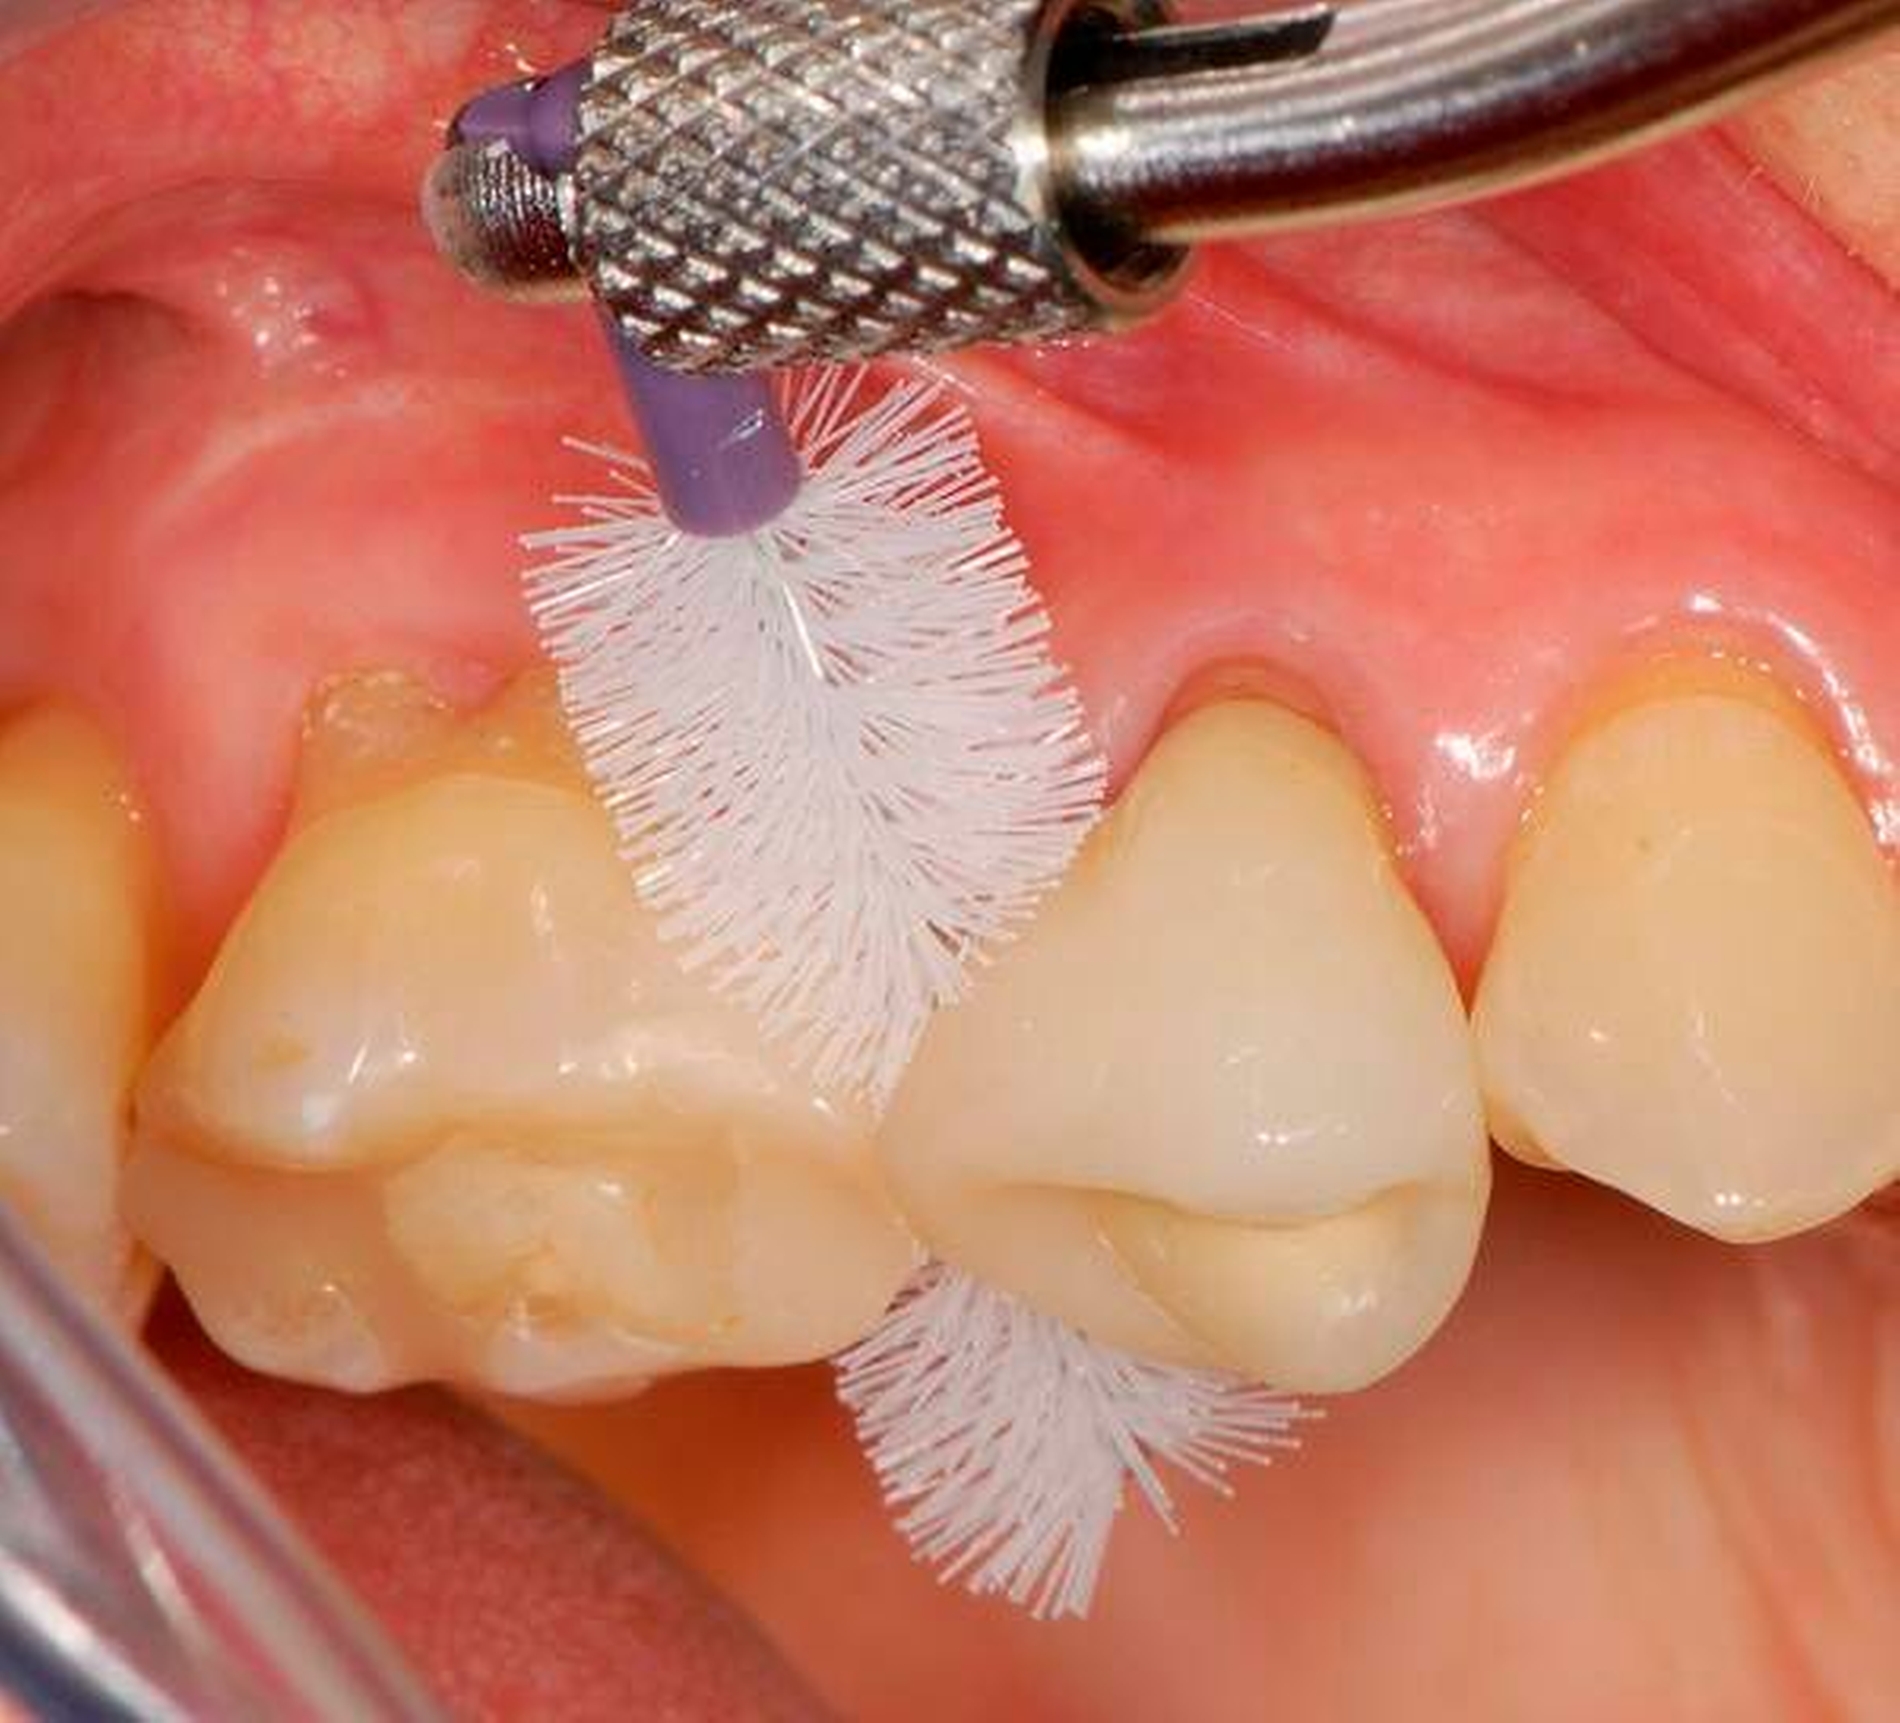

Mundhygiene

Low cost: zum Beispiel Handzahnbürste ohne individuell ausgewählte Interdentalraumbürsten (IDR-Bürsten)

Frugal: zum Beispiel Handzahnbürste und zusätzlich individuell ausgewählte IDR-Bürsten

Premium: zum Beispiel elektrische Zahnbürste (oftmals wird dabei bemerkenswerterweise auf IDR-Bürsten verzichtet, wobei eine so herbeigeführte Kostenreduktion für viele Menschen allerdings keine gute Entscheidung wäre, siehe unten)

Wenn man die die Zahnmedizin betreffenden direkten und indirekten Werbeaktivitäten von Industrieunternehmen beobachtet, fällt auf, dass zwei Bereiche dominieren und zwar nicht nur im Hinblick auf PR-Maßnahmen aller Art für die Profession, sondern auch für die Bevölkerung. Zum einen handelt es sich um umfangreiche Aktivitäten zur Steigerung von Implantatversorgungen, zum anderen um die Verkaufsausweitung elektrischer Zahnbürsten. In beiden Fällen wird oftmals der Hightech-Charakter herausgestrichen. Unter bestimmten Versuchsbedingungen schneiden elektrische Zahnbürsten zwar etwas besser ab als Handzahnbürsten. Sichtet man allerdings die Literatur genauer, ist man gut beraten, mit der Interpretation vorsichtig zu sein. Ganß schrieb dazu in einer aktuellen Übersichtsarbeit zum Thema „Zähneputzen – Mythen und Wahrheiten“: „Die Überlegenheit elektrischer Bürsten gegenüber Handzahnbürsten konnte bislang nicht nachgewiesen werden“ [Ganß, 2016]. Bedenklich erscheint es, wenn Hersteller elektrischer Zahnbürsten suggerieren, man könne mit diesen Hilfsmitteln die Interdentalräume suffizient reinigen. Dies ist nämlich nicht ganz korrekt. Viele Menschen benötigen besondere zusätzliche Hilfsmittel zur Interdentalraumhygiene, wobei individuelle Instruktions- und Trainingsmaßnahmen unabdingbar sind. Da diese oftmals nicht in Anspruch genommen werden (können), verwundert es kaum, dass sich hier Effekte kaum aussagekräftig messen lassen.

Wenn beispielsweise ein Patient mit tiefen Zahnfleischtaschen Interdentalraumbürsten anwendet, die ohne nennenswerten Widerstand die Zahnzwischenräume passieren, kann man nicht erwarten, dass ihm dies zu einem großen Nutzen für die Zahngesundheit verhilft. Dies betrifft auch Implantatträger [Staehle et al., 2016]. In Abbildung 7 ist ein Patient gezeigt, der trotz Parodontalbehandlung und regelmäßiger Reinigung mit einer – zu dünnen – Interdentalraumbürste hohe Sondierungstiefen und Bluten nach Sondieren aufwies. Erst nach Umstellung auf eine größere Interdentalraumbürste mit längeren Seitenborsten und einem genügend hohen Passagewiderstand durch den Interdentalraum wurde der Taschenfundus mit den Borsten besser erreicht und es kam zu einem deutlichen Entzündungsrückgang.

Eine zahnmedizinisch sinnvolle frugale Intervention für viele Menschen wäre, ihnen eine Handzahnbürste zu empfehlen und dies bedarfsgerecht durch geeignete Interdentalraumbürsten zu ergänzen. Dies wäre in manchen Fällen wesentlich besser, als jemanden durch die alleinige Empfehlung einer elektrischen Hightech-Zahnbürste in einer falschen Sicherheit zu belassen und auf Interdentalraumbürsten zu verzichten. Allerdings muss man einräumen, dass derzeit Interdentalraumbürsten relativ teuer und verschleißanfällig sind und dass das oft sehr unübersichtliche und unvollständige Produktangebot nicht den tatsächlichen Erfordernissen genügt. Insofern besteht hier auch von Herstellerseite Handlungsbedarf.